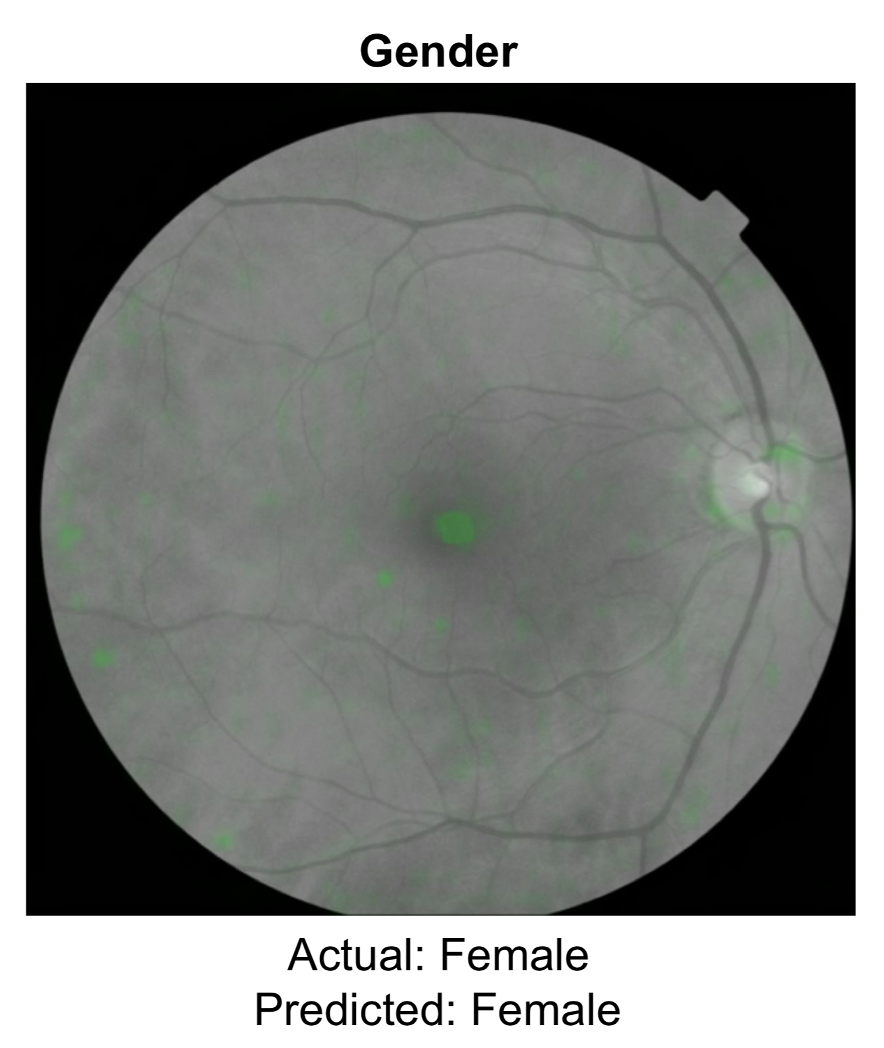

First, a review on deep learning from the retina. We should have known a few years back that something was rich (dare I say eye-opening) about the retina that humans, including retinal experts, couldn’t see. While there are far simpler ways to determine gender, it’s a 50-50 toss up for ophthalmologists, which means there are no visible cues to human eyes. But now two models have shown 97% accuracy of gender determination from neural network training. That was just the beginning.

Of course, AI models have been shown to be quite useful for detecting eye diseases, such as diabetic retinopathy. But this is about the indirects, the not so obvious. That work has now extended to detection of kidney disease, control of blood glucose and blood pressure, hepatobiliary disease, a previous study on predicting heart attack, close correlation of the retinal vessels with the heart (coronary) artery calcium score, and, prior to the new report above, the ongoing prospective assessment and tracking of Alzheimer’s disease (“AlzEye,” Moorfields Eye Institute, UK, led by Professor Pearse Keane).

Nearly all of this work has been published in the last couple of years, and there’s no telling what else can be seen by machines that would be invisible to human eyes. Therein lies the future potential for taking a photo of your retina via your smartphone (ideally without having to dilate your pupils) to get an accurate readout of many of your body systems/ organ functions.